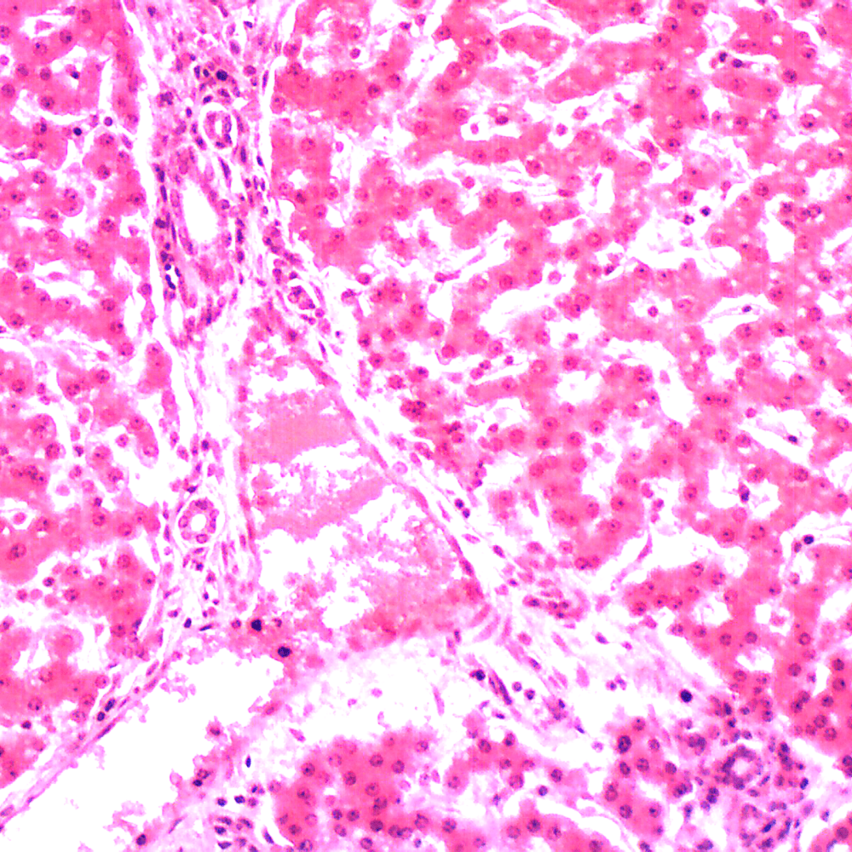

5 Prepared Slides, Blood and Guts (mixed), mounted on glass with cover slips, labeled and shipped with plastic storage case.

Inspired by a permanent exhibition at The Natural History Museum in London, these new sets of prepared slides are designed to stimulate the imagination of children - and adults alike! They are professional grade slides and an excellent introduction to the microscopic world.

Human Blood (sm)

Cerebellum (sec)

Liver (sec)

Spinal Cord (c.s)

Heart (sec)